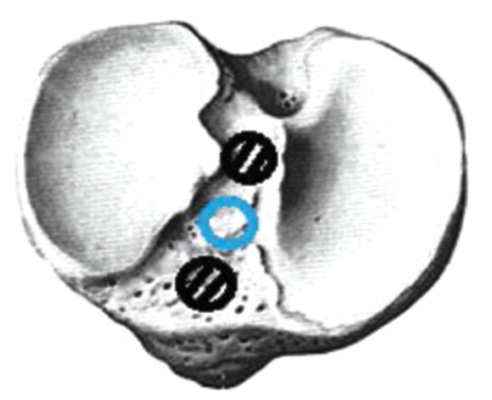

The actual revision surgery was similar to the primary ACL plastic surgery, and achieving the correct anatomical location of the channels was the focus. Since the landmarks were less clear than that in primary plastic surgery, the PCL attachment site was a landmark for the tibial channel location, and the new channel was tried to be placed in the middle and slightly medial to the intercondylar eminence. When the primary intraosseous channel was located outwardly in the tibia, we formed inwardly a new channel of a larger diameter and centered the graft in the channel using a BioIntrafix sleeve (DePuy Mitek, USA) (Fig. 1).

Fig. 1. The location of the primary tibial canal outward, — correct channel placement.

When the primary channel was displaced inwards, the graft was removed, a screw was inserted there, and a new channel with a diameter of 6–7 mm was formed. The screw was inserted to not break the wall of the new channel (Fig. 2).

Fig. 2. The location of the tibial canal inside, — correct channel placement.

If the primary channel was located anteriorly or posteriorly (Fig. 3), a standard channel in the tibial bone was performed. When making a channel of a larger diameter, the graft was centered in the channel using Milagro screws (DePuy Mitek, USA).

Fig. 3. Variants of the location of the tibial canals, — correct channel placement.

During the revision of ACL reconstruction, in 1 (1.1%) case, the location of the tibial channel was near the anterior horn of the internal meniscus (Figs. 4, 5).

Fig. 4. Location of the tibial canal near the anterior horn of the meniscus.

Fig. 5. Channel layout.